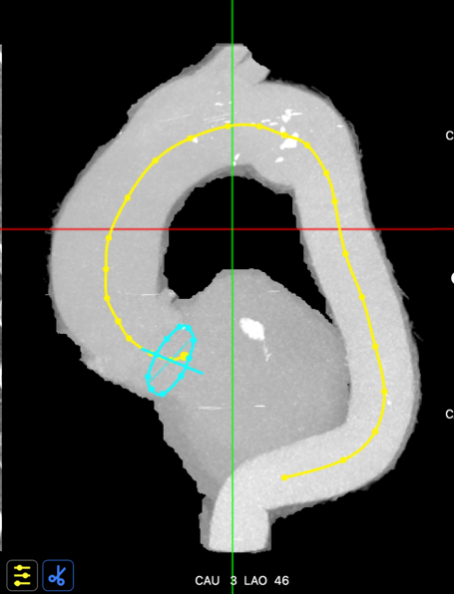

主动脉入路评估

主动脉弓矢状位

主动脉弓冠状位

血管入路三维